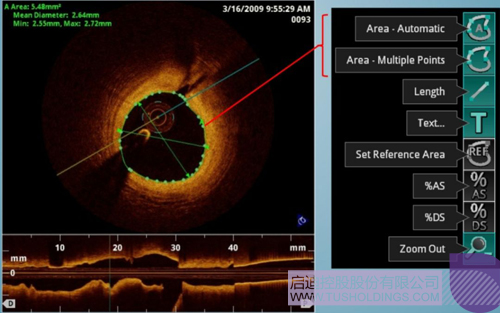

光学相干断层成像技术(OCT)是一种新型影像技术,它利用弱相干光干涉仪的基本原理,检测生物组织不同深度层面对入射弱相干光的背向反射或几次散射信号,通过扫描,可得到生物组织二维或三维结构图像。OCT由于具有极高的分辨率(10 um),可以对内膜性质和支架结构更加精确地辨别和分析。

在冠脉介入治疗迅猛发展的今天,随着复杂病变患者日益增多,血管内影像扮演了越来越重要的角色。OCT借助其高分辨率的图像优势,可以提供更清晰的病变特征和支架植入情况,OCT存在以下优势:可更精确的检测介入治疗后的血管内情况,如夹层、支架贴壁不良、组织脱垂等,另外,它在管腔直径和面积方面的测量精度更高。

血管腔内精准评估